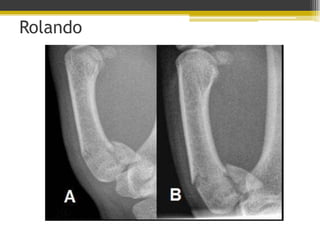

Fractura de

Rolando

• Fractura intraarticular con tres

fragmentos.

• Base del primer metacarpiano

• Dificil de reducir.